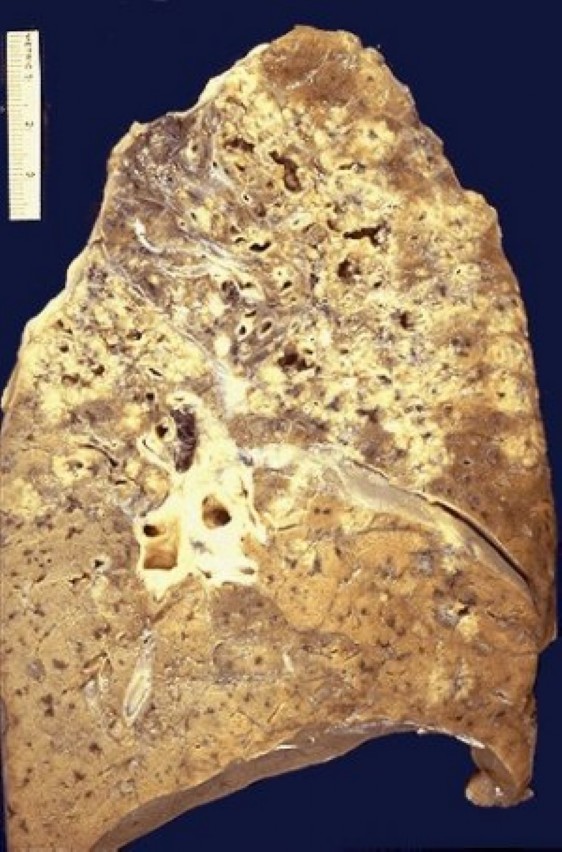

Медицинские аспекты заболеваний: рентгенологическая картина туберкулеза костей

Раздел: Снимки-откровения